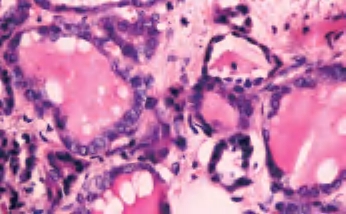

3.镜下 为复杂分支状乳头,含纤维血管轴心,细胞拥挤,核增大,呈卵圆形、沙砾体,表面被以单层柱状上皮,半数以上核呈毛玻璃样,有核沟,核内假包涵体(图3-40至图3-43)。

图3-42 甲状腺乳头状癌,箭头处核内假包涵体